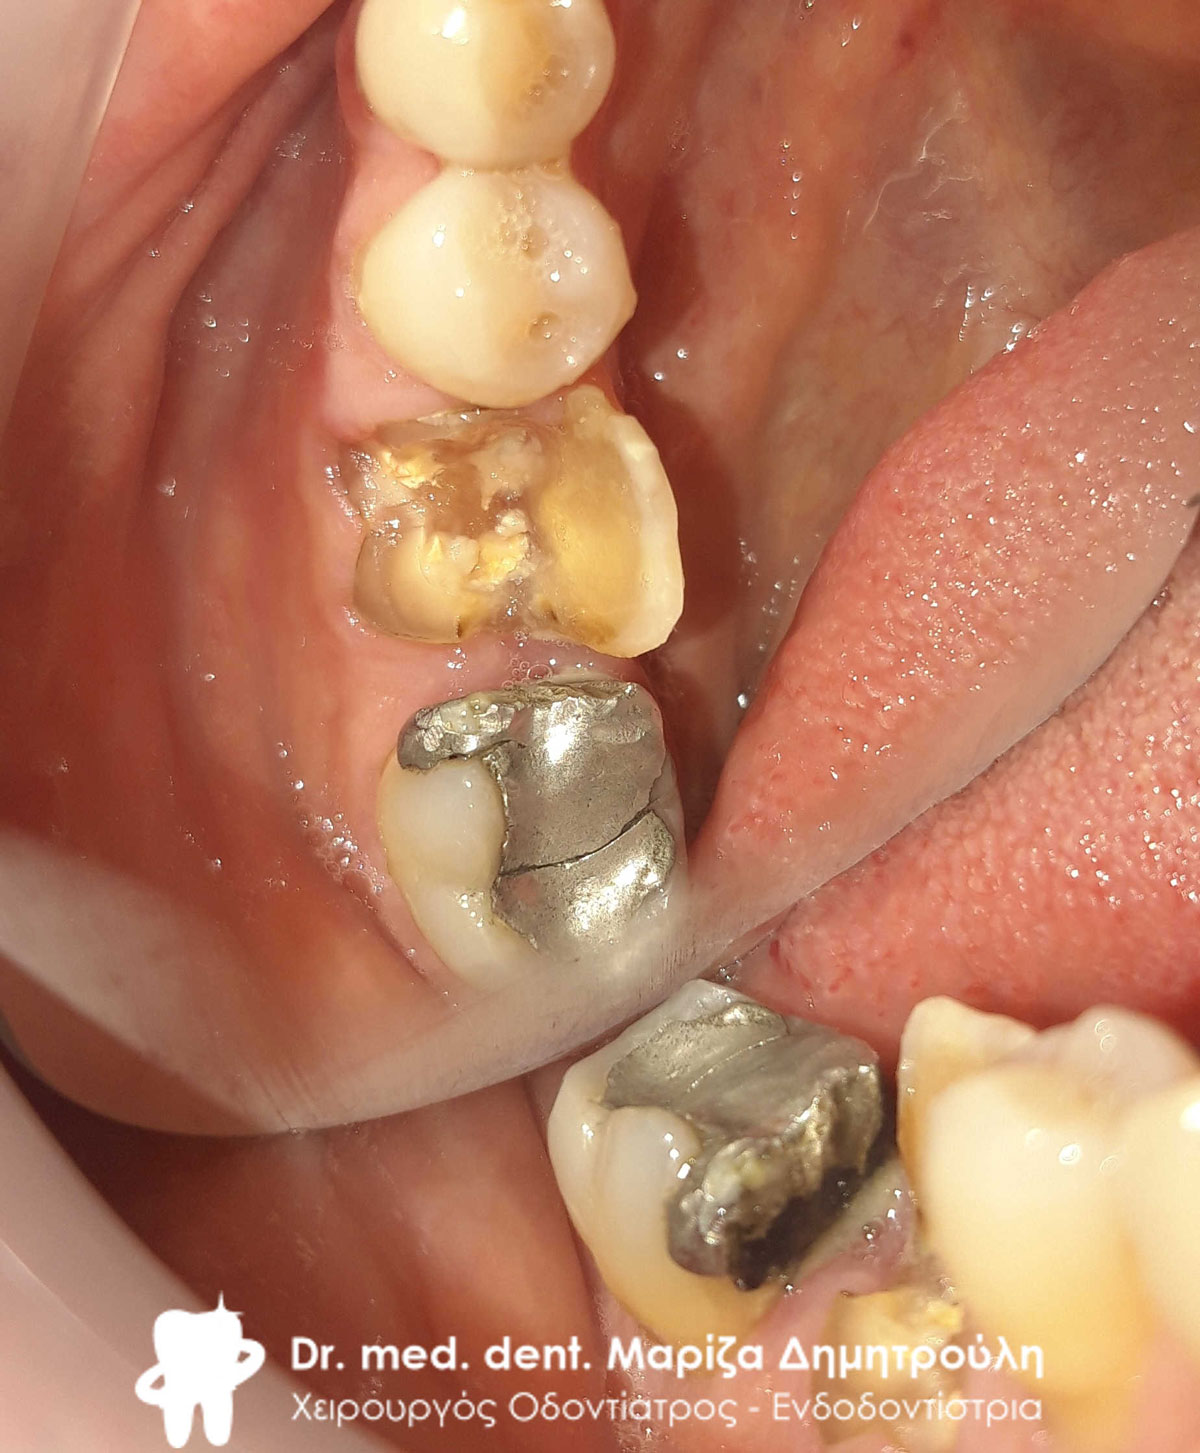

Περιστατικό – Ολοκεραμικές θήκες ζιρκονίου στην αριστερή πλευρά της άνω γνάθου

Ο ασθενής είχε δύο παλιές μεταλλοκεραμικές θήκες, οι οποίες με την πάροδο του χρόνου τερηδονίστηκαν, φθάρθηκαν (είχε φθαρεί η κεραμική κάλυψη των θηκών) και έπρεπε να αντικατασταθούν με νέες (απουσιάζει η φωτογραφία της αρχικής εικόνας). Εφόσον αφαιρέθηκαν οι παλιές θήκες πραγματοποιήθηκαν όλες οι απαραίτητες οδοντιατρικές εργασίες (απονεύρωσεις δοντιών, ανασύστασεις / σφραγίσματα δοντιών) όπου ήταν απαραίτητο, προκειμένου να κατασκευαστούν νέες ολοκεραμικές θήκες ζιρκονίου.

Στο μεσοδιάστημα που μεσολάβησε ώστε ο οδοντοτεχνίτης να κατασκευάσει τις νέες θήκες δοντιών, τα τροχισμένα δόντια ήταν προστατευμένα με προσωρινές στεφάνες.

Η νέα γέφυρα είχε ένα πολύ καλό αισθητικό και λειτουργικό αποτέλεσμα.

Αρχική εικόνα των δοντιών μετά την αφαίρεση της παλιάς γέφυρας

Τα δόντια μετά τις απαραίτητες απονευρώσεις και τις ανασυστάσεις

ΤΕΛΙΚΗ ΕΙΚΟΝΑ